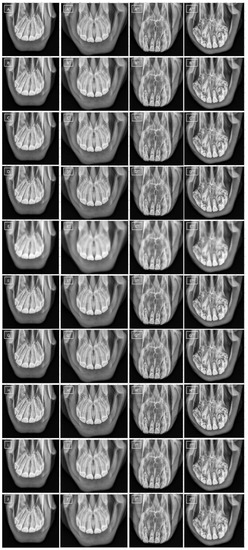

2.2. Image Collection

2.3. Image Processing

2.3.1. Masks Annotation and Image Segmentation

2.3.2. Filtering